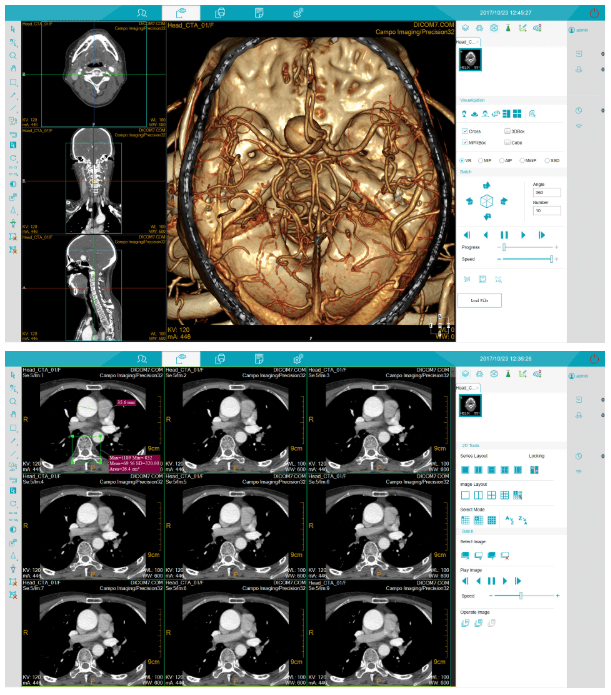

MSLCTX10 CT system is completely developed by Campo Imaging. It is the first CT product of Campo Image. P-Axial is a patent of MSLXTX10 CT system. It can obtain the thinnest CT images in the 0.275mm and has obvious advantages in the application of inner ear imaging and pulmonary nodule detection. 32-slice dual energy imaging extended the application of CT dual energy imaging. MSLXTX10 CT system provides high quality images and stable performance which can help hospitals to achieve comprehensive accurate diagnosis, and it will redefine the new standards of 32-slice CT imaging.